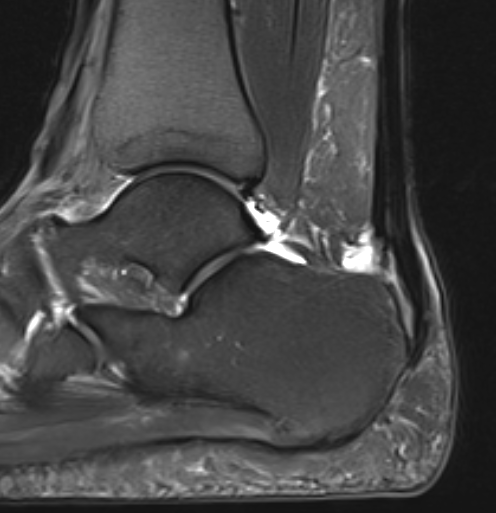

Retrocalcaneal bursitis with Haglund's

Partial tearing at insertion with retrocalcaneal bursa

Tendon thickening, Haglund's deformity and retrocalcaneal bursa